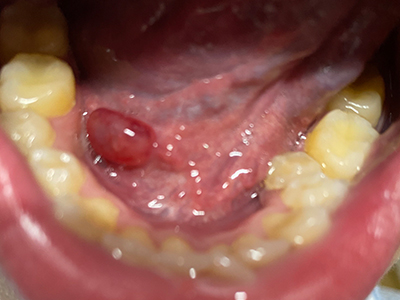

舌下腺囊肿舌底下长了个蚕豆大小的疙瘩图

舌下腺囊肿出现在舌系带一侧,表现为凸出于黏膜表面的疙瘩,如蚕豆大小,质地较软,有异物感,局部自发破溃,流蛋清样液体,常反复出现。